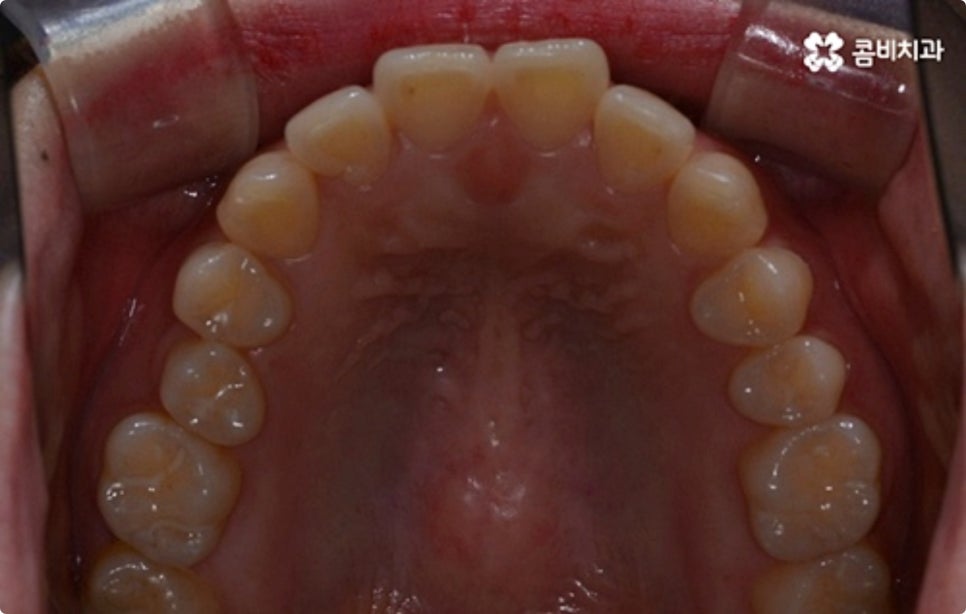

클리피씨 교정도 치아 색상의 세라믹 재질을 사용하기 때문에 심미성이 높은 편이지만 만약에 장치가 아예 겉으로 드러나지 않았으면 좋겠다고 생각하신다면 브라켓을 치아 안쪽에 부착하는 설측교정을 이용할 수 있는데요. 하지만 설측교정은 혀와 맞닿는 부분의 이물감, 통증, 발음상 문제 등을 일으킬 수 있기 때문에 잘 보이는 윗니는 설측으로, 잘 드러나지 않는 아랫니는 보통 교정과 같이 순측 (입술쪽) 으로 진행하는 콤비교정을 통해 이를 보완할 수 있어요. 사진에서 살펴보실 수 있는 케이스 역시 이렇게 콤비로 진행한 직장인치아교정 과정으로 시간이 지날수록 점차 치열이 가지런해지고 교합이 올바르게 개선되는 것을 확인해 보실 수 있습니다.